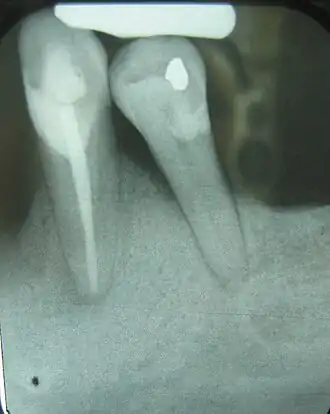

This X-ray film displays a horizontal defect.

This X-ray film displays two lone-standing mandibular teeth, #21 and #22: the lower left first premolar and canine, exhibiting severe bone loss of 30-50%. Widening of the PDL surrounding the premolar is likely due to secondary oclcusal trauma.